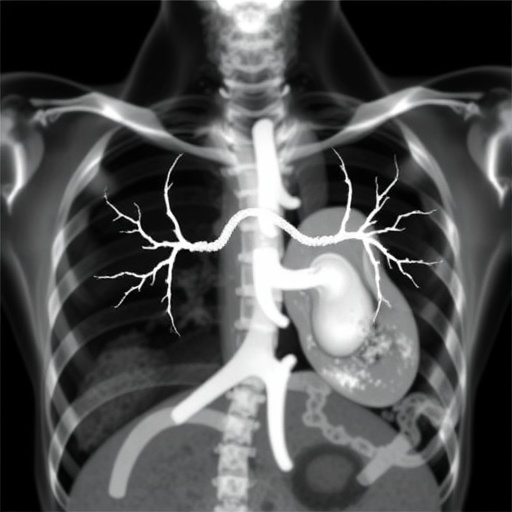

In a groundbreaking study that promises to deepen our understanding of Duchenne muscular dystrophy (DMD) and its devastating cardiac complications, researchers have unveiled compelling evidence illustrating how the variant burden in genetic makeup influences the severity of cardiomyopathy in patients with DMD-related Duchenne muscular dystrophy. This revelation, published in Pediatric Research in early 2026, offers novel insights that could pave the way for more targeted therapeutic approaches and significantly improve prognostic stratification in affected individuals.

DMD, a severe X-linked recessive neuromuscular disorder, is characterized by progressive muscle degeneration caused by mutations in the dystrophin gene. While skeletal muscle deterioration has long been the focus of clinical attention, cardiomyopathy emerges as a critical determinant of morbidity and mortality in these patients. However, the underpinning molecular mechanisms that modulate the severity of cardiac involvement have remained elusive, challenging clinicians in predicting disease progression and tailoring treatments.

Importantly, the researchers employed state-of-the-art bioinformatics pipelines to dissect the variant burden with remarkable resolution. This approach enabled them to identify modifier genes and pathways implicated in cardiomyopathy, extending our knowledge beyond the canonical dystrophin network. Notably, the analysis revealed that patients harboring a higher number of deleterious variants experienced more pronounced cardiac abnormalities, as measured by metrics such as left ventricular ejection fraction and fibrosis extent. These correlations signify that variant burden is not merely a genetic footnote but a pivotal determinant that modulates phenotypic expression in Duchenne muscular dystrophy.